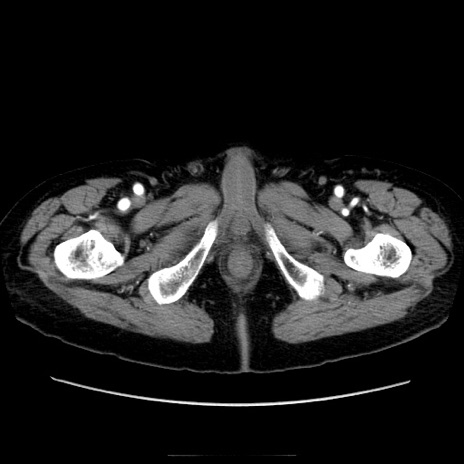

症例21(横断像)

【症例】70歳代男性

【主訴】腹痛

【現病歴】肝硬変・肝細胞癌にてかかりつけの方。約9時間前に食後より腹痛出現。症状が徐々に増悪し、嘔吐出現したため来院。

【既往歴】肝硬変、肝細胞癌(RFA、TACE後)

【身体所見】意識清明、表情苦悶様、BT 36℃、BP 129/78mmHg、P 88bpm、SpO2 97%(RA)、右上腹部から心窩部にかけて圧痛あり、反跳痛なし、筋性防御あり。

【データ】WBC 5800、CRP 0.16